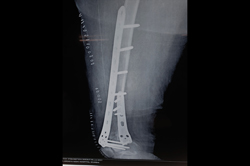

Subtrochanteric Fracture